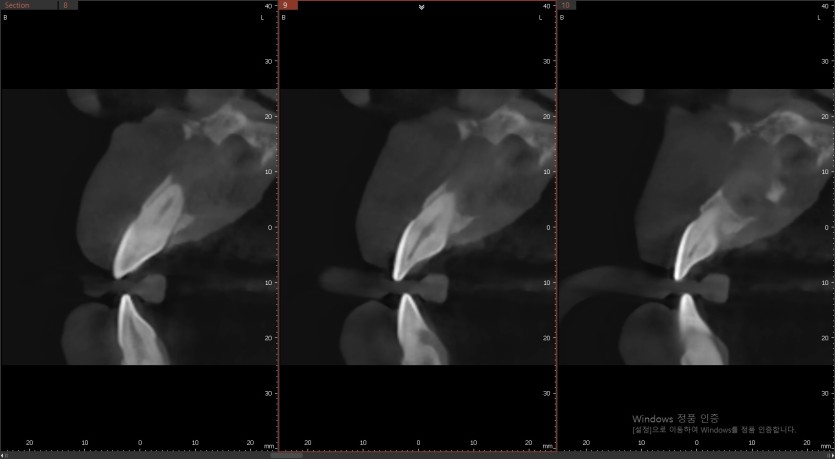

매복 과잉치와 낭종을 제거하고 치조골 이식을 진행하였습니다.